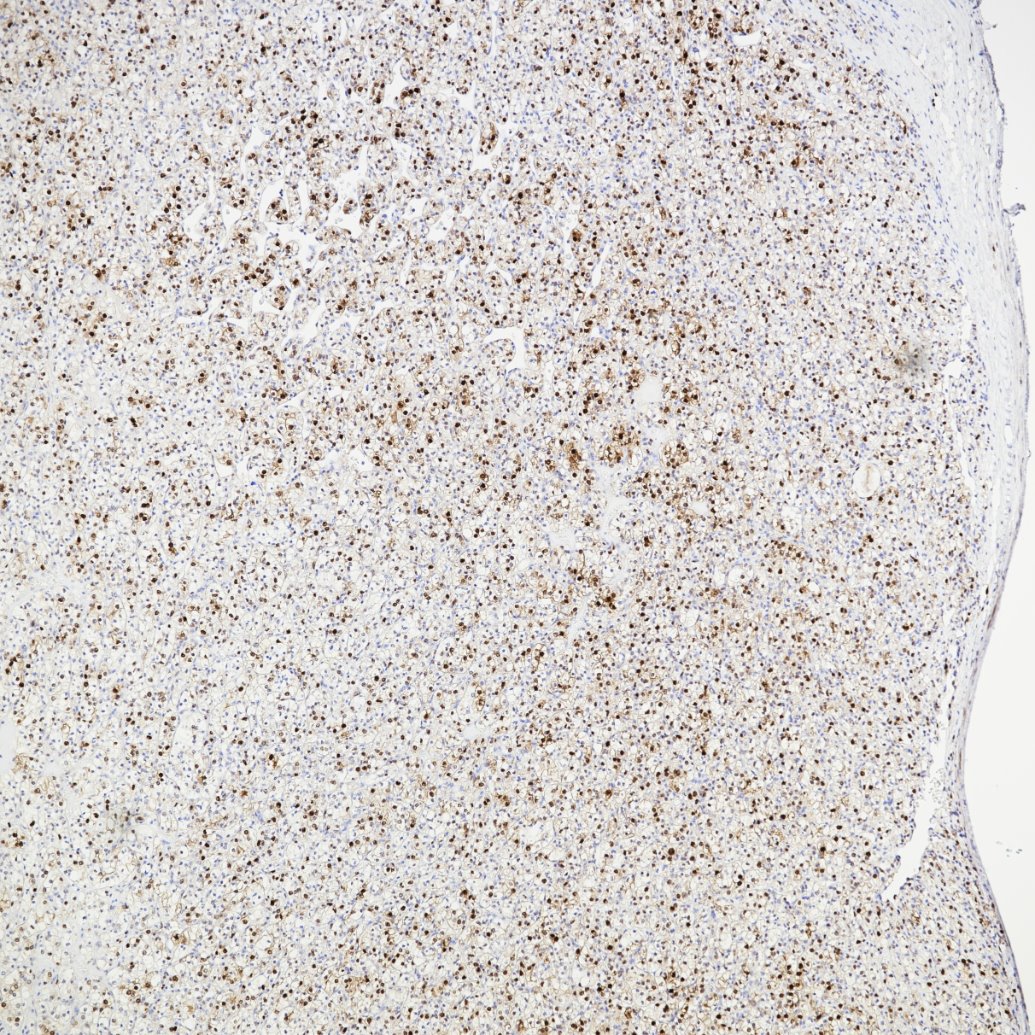

| Positive IHC-Autostainer detected in | human renal cell carcinoma tissue |

| Positive IHC detected in | human oesophagus cancer tissue, human tonsillitis tissue Note: suggested antigen retrieval with TE buffer pH 9.0; (*) Alternatively, antigen retrieval may be performed with citrate buffer pH 6.0 |

| Immunohistochemistry (IHC) | IHC : 1:500-1:2000 |